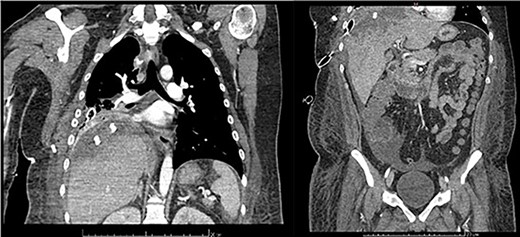

Examination revealed tachycardia, tachypnea, jaundice, dehydration, jugular vein distension, right lung hypoventilation, ascites, upper abdominal tenderness and bilateral lower limb edema. Laboratory workup highlighted neutrophilic leukocytosis, with WBCs exceeding 20 000/μl, along with an abnormal hepatic function panel. The latter showed hypertransaminasemia with ALT predominance over AST (344.7 U/L and 288.5 U/L, respectively), hyperbilirubinemia (10.01 μmol/L) and elevated values of ALP (909.1 U/L) and DHL (709.9 U/L). Of relevance, creatinine elevation (2.11 mg/dl), thrombocytosis (629 × 109/L) and positive D-Dimer (5780 ng/ml) were also noted, so acute kidney injury management and thromboprophylactic measures were initiated. A chest X-ray (CXR) showed a massive right pleural effusion (Fig. 1) and an abdominal ultrasound (US) revealed hepatomegaly with a right nodule (Fig. 2). After further evaluation, tomographic evidence of a right pleural effusion occupying 100% of the lung (Fig. 3) and a 20 cm hypodense, nodular lesion in the right liver (Fig. 4) were identified. These findings were suggestive of an ALA concomitant with an empyema. The patient was admitted into the intensive care unit and prepared for surgery.

Frontal chest CT at admission: right pleural effusion occupying 100% of the lung.

Axial abdominal CT at admission: 20 cm nodular lesion occupying the right liver lobe.

Frontal thoraco-abdominopelvic CT at 9 days after surgery: subpleural collection of 79 × 34 mm, heterogenous, hypodense hepatic lesion with contrast enhancement on its borders, fluid collection around the liver, paracolic gutters and pelvic cavity.